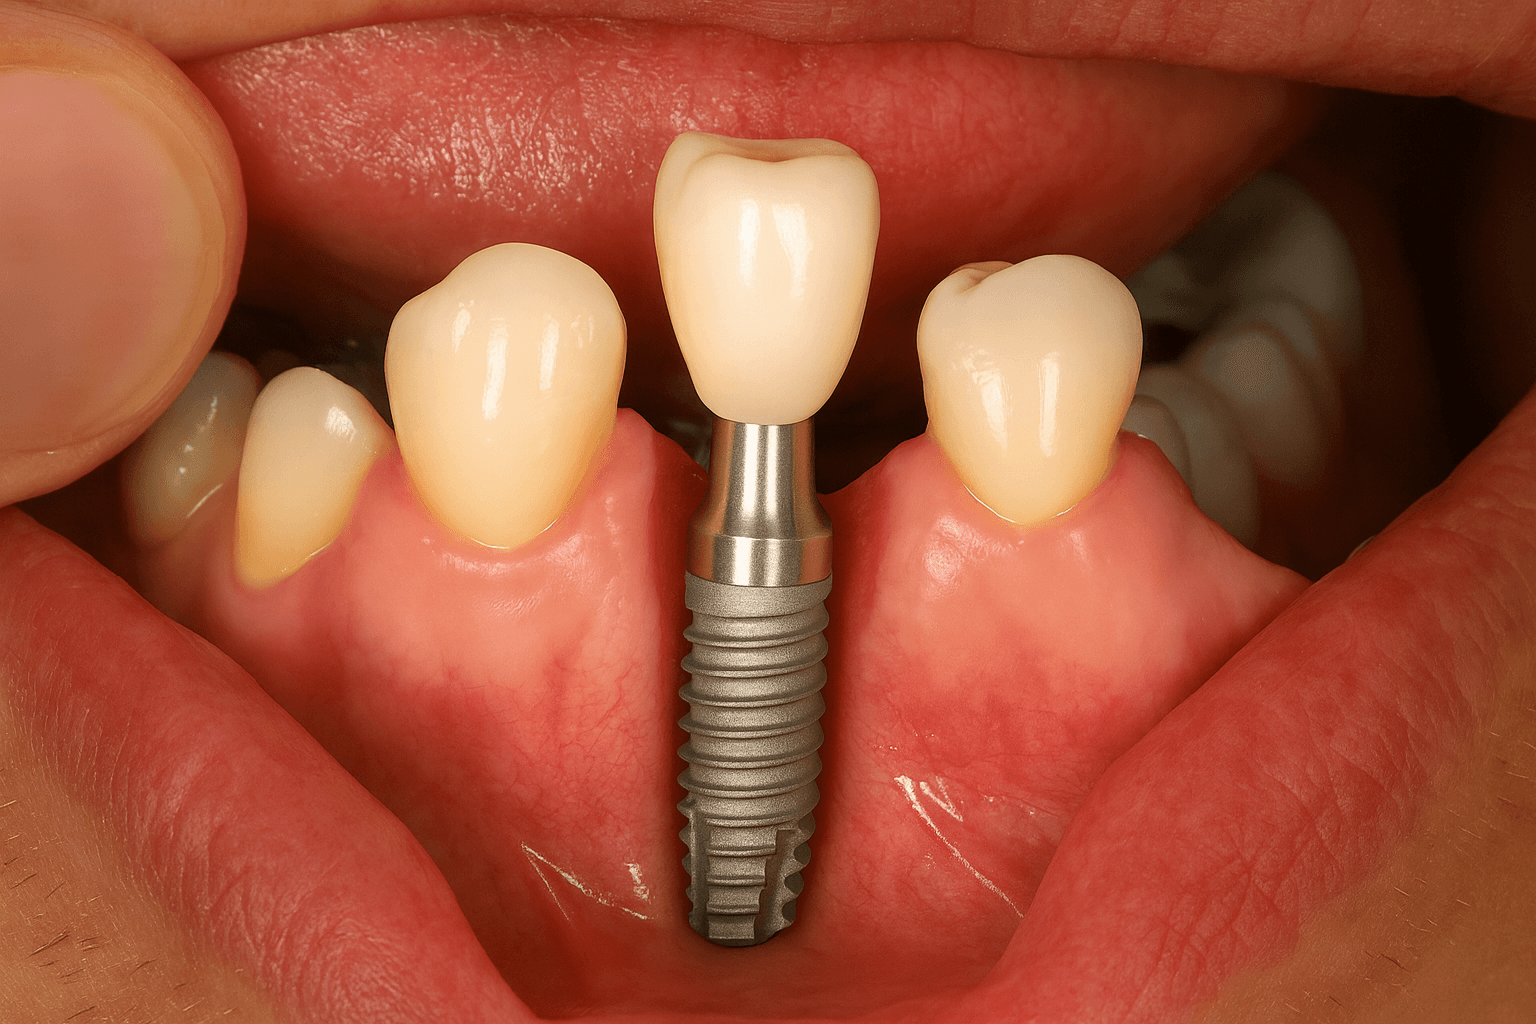

歯科用インプラントとは、失われた歯の機能を補うために顎の骨に埋め込む人工の歯根のことを指します。

インプラント本体は外科的処置によって顎の骨に埋入され、その後6〜24週間ほどの治癒期間を経て骨としっかり結合します。この結合によって、天然歯に近い安定性と機能を取り戻すことが可能になります。

インプラント

そして、3つ目がインプラントです。

インプラントは、ブリッジのように隣の健康な歯を削ったり、支えとして負担をかけたりする必要がありません。また、入れ歯のような装着時の違和感や、咬み合わせのズレ、痛みなどもほとんどなく、快適な使用感が得られます。

とくに前歯の場合は、自然な見た目や表情を取り戻すことができるため、人前でも自信をもって話したり笑ったりできます。金具(クラスプ)などが見えてしまう心配もありません。